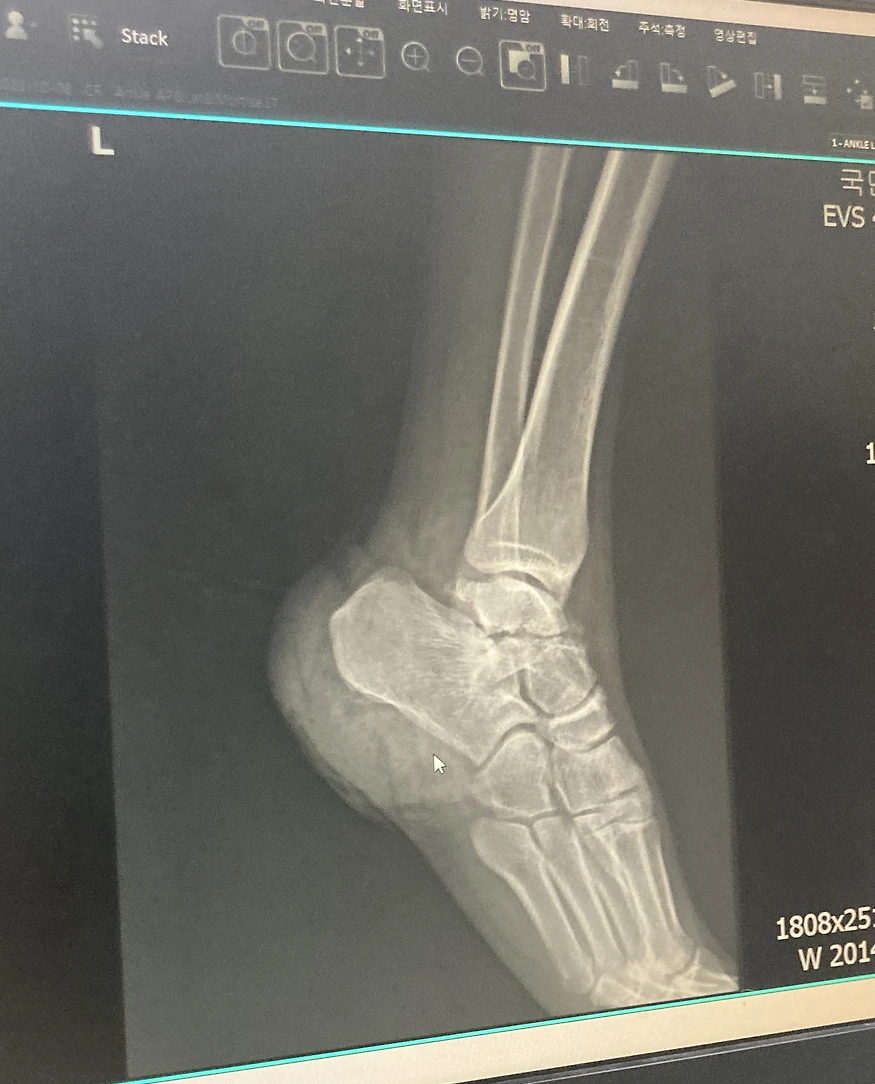

구급대원과 함께 근처 제일 큰 정형외과로 향했다. 그곳이 흉터 없이 잘 꿰맨다고, 그때 가지만 해도 구급대원들도 그냥 찢어진 상처쯤으로 알고 있었던 것 같다. 이송 중 발가락을 움직여보니 두둑 하는 소리가 들렸지만 심각하게 받아들이지는 않았다. 사고날이 휴일임에도 불구하고 응급실을 운영하는 병원이 있어서 다행이라고 생각했다. 의사 선생님을 보기 전 엑스레이를 찍었다. 그리고 선생님을 보러 갔다.

선생님은 뜻밖의 말을 했다. 많이 다치셨다고. 엑스레이를 보여주며 왼발의 정강이 뼈와 발사이에 동그란 뼈가 분쇄 골절로 두 동강이 낫다는 것이었다. 그리고 당장 응급수술을 해야 한다고 했다. 선생님은 오늘이 휴일이라 수술을 세팅하려면 여러 사람들을 불러 모아야 한다고 빨리 결정해야 한다고 했다. 그럼에도 불구하고 나는 갑자기 큰 수술을 해야 한다고 하니까 겁이 나서 수술을 일단 미뤘다.